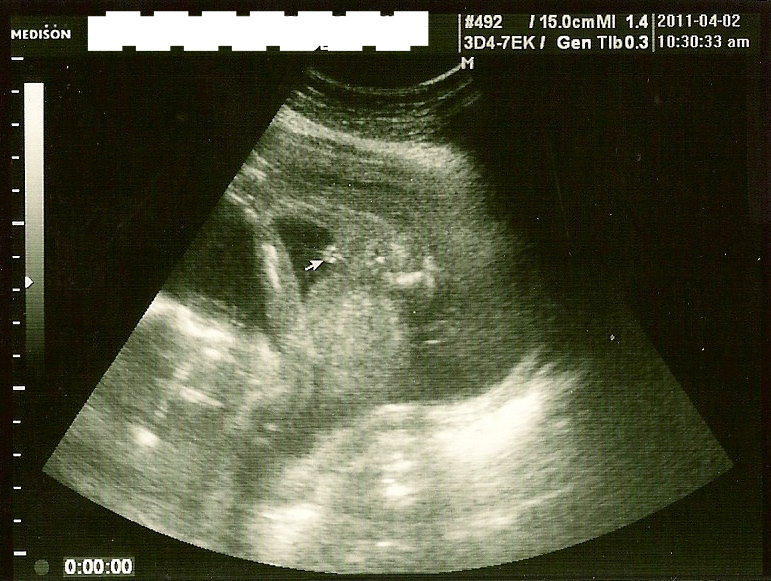

19週6日です。 男の子でした笑かなり丸まってもう、はっきり腕がわかります★ 302グラムで標準でした★ ※ちなみに5人目になります BPDは416。 ほぼ週数通りの大きさで順調とのこと (ω)

男の子の性別判定はいつから可能? 男の子の性別判定はいつから可能なのでしょうか? 男の子の性別判定は比較的早く、早くて15週・16週ごろからシンボルが見えてくる ようです! 私 多分これは男の子だね~ と先生に言われ、性別が判明したものの確定とはならず。, 妊娠19週6日の検診で、予想通り男の子と確定しました!, !, !, 妊娠初期 (11週、12週、13週)ベ